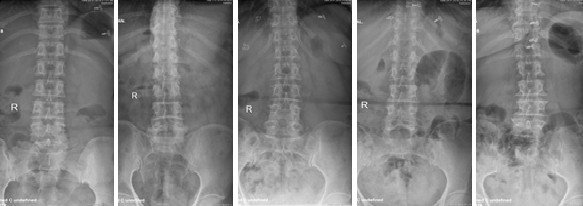

In the medical era, health of a bone is accessed by the bone mineral density (BMD) test. Bone fracture risk in the humans are estimated or evaluated by the BMD test. The test statement recognizes the presence of signs of presence of the frequent occurring disease in the bone called as osteoporosis. So it is obligatory to enclose a customary database in X-Ray images for the young bud researchers to capture up the dealings to the advance stage by accurate examination of the medical results of the images. The projected X-Ray database is termed XSITRAY, characterizes an early attempt to offer a group of X-Ray images of Spine, Femur, Clavicle, Extremity & Ankle, Extremity & Hand and Knee bones. The details such as age, gender and unique Id of the patient are interpreted in the database.

In this database, for every image, Annotation is provided for following attributes: age, gender and unique Id of the patient.

Fathima S. M. N, Tamilselvi R, Beham M. P. XSITRAY: A Database for the Detection of Osteoporosis Condition. Biomedical & Pharmacology Journal, March 2019; 12(1). DOI: http://dx.doi.org/10.13005/bpj/1637